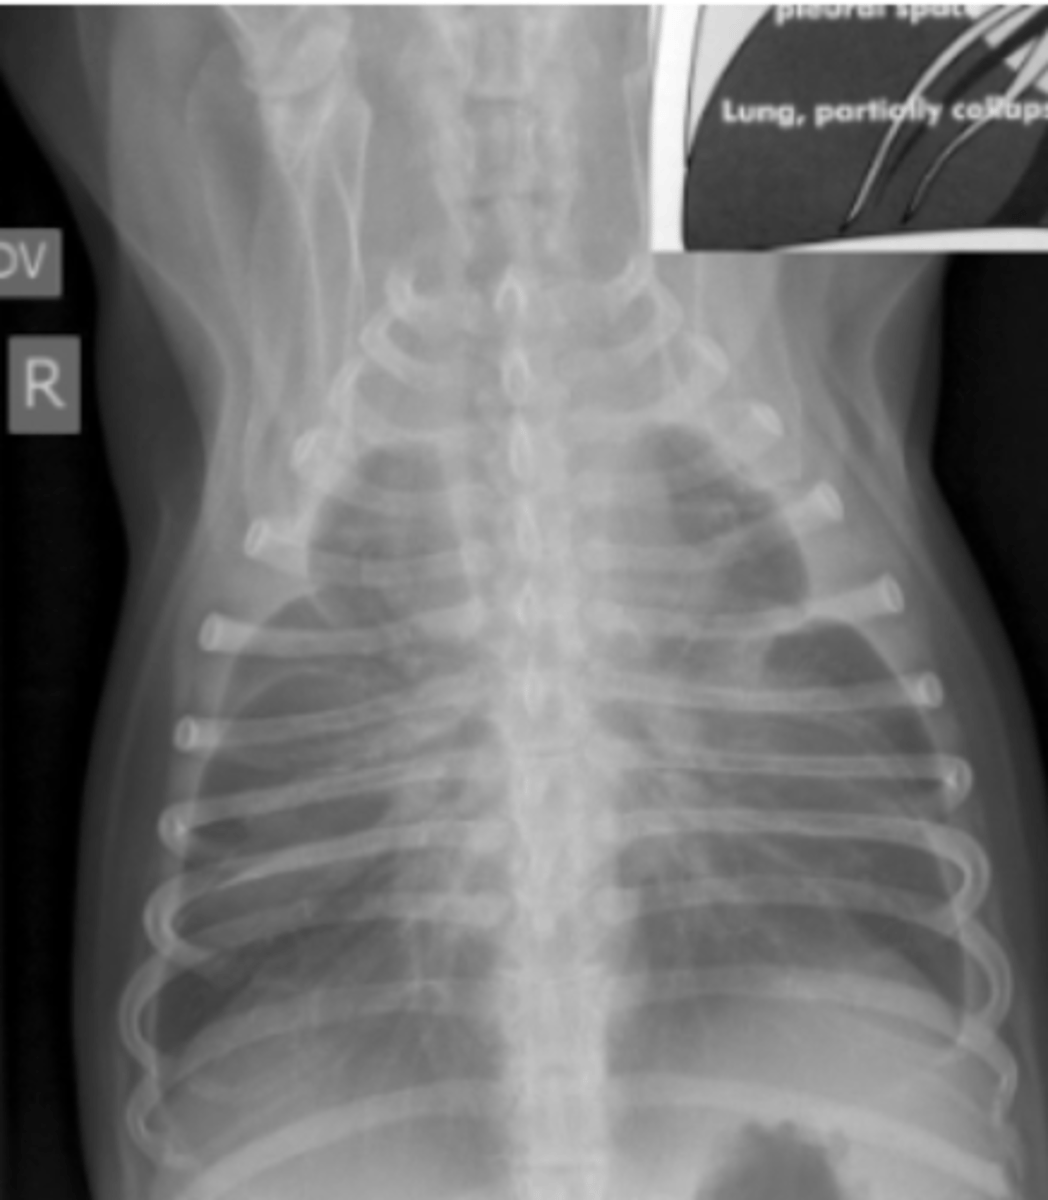

efusión pleural

patología: